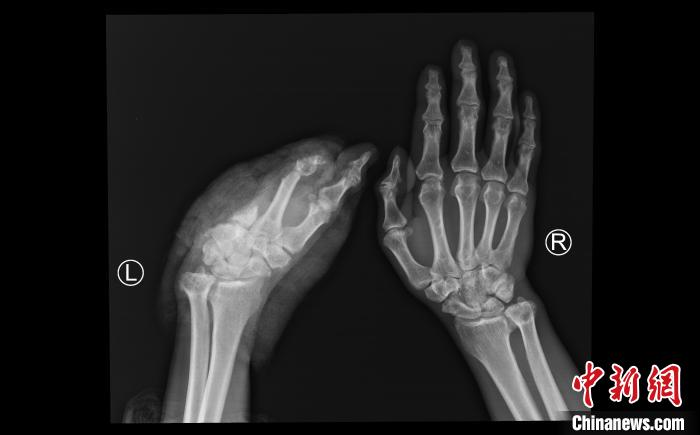

患者断掌ct影像.四川省人民医院供图

左手掌第5掌骨基底部粉碎性骨折

一例掌骨骨折伴脱位